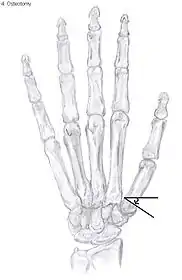

Showing the forces after trapeziectomy

Osteotomy of the thumb

Metacarpal osteotomy

The aim of metacarpal osteotomy is to change the pressure distribution on the TMC joint. The hope is that this will slow the pace of development of osteoarthritis. There is no evidence that this procedure can modify the natural course of TMC OA. Osteotomy may be considered for people with mild arthritis.[24]

During osteotomy, the metacarpal is cut and a wedge shape bone fragment is removed to move the bone away from the hand.[36] Postoperative, the thumb of the patient is immobilized using a thumb-cast.

Possible complications are non-union of the bone, persistent pain related to unrecognized CMC or pantrapezial disease and radial sensory nerve injury.[24]